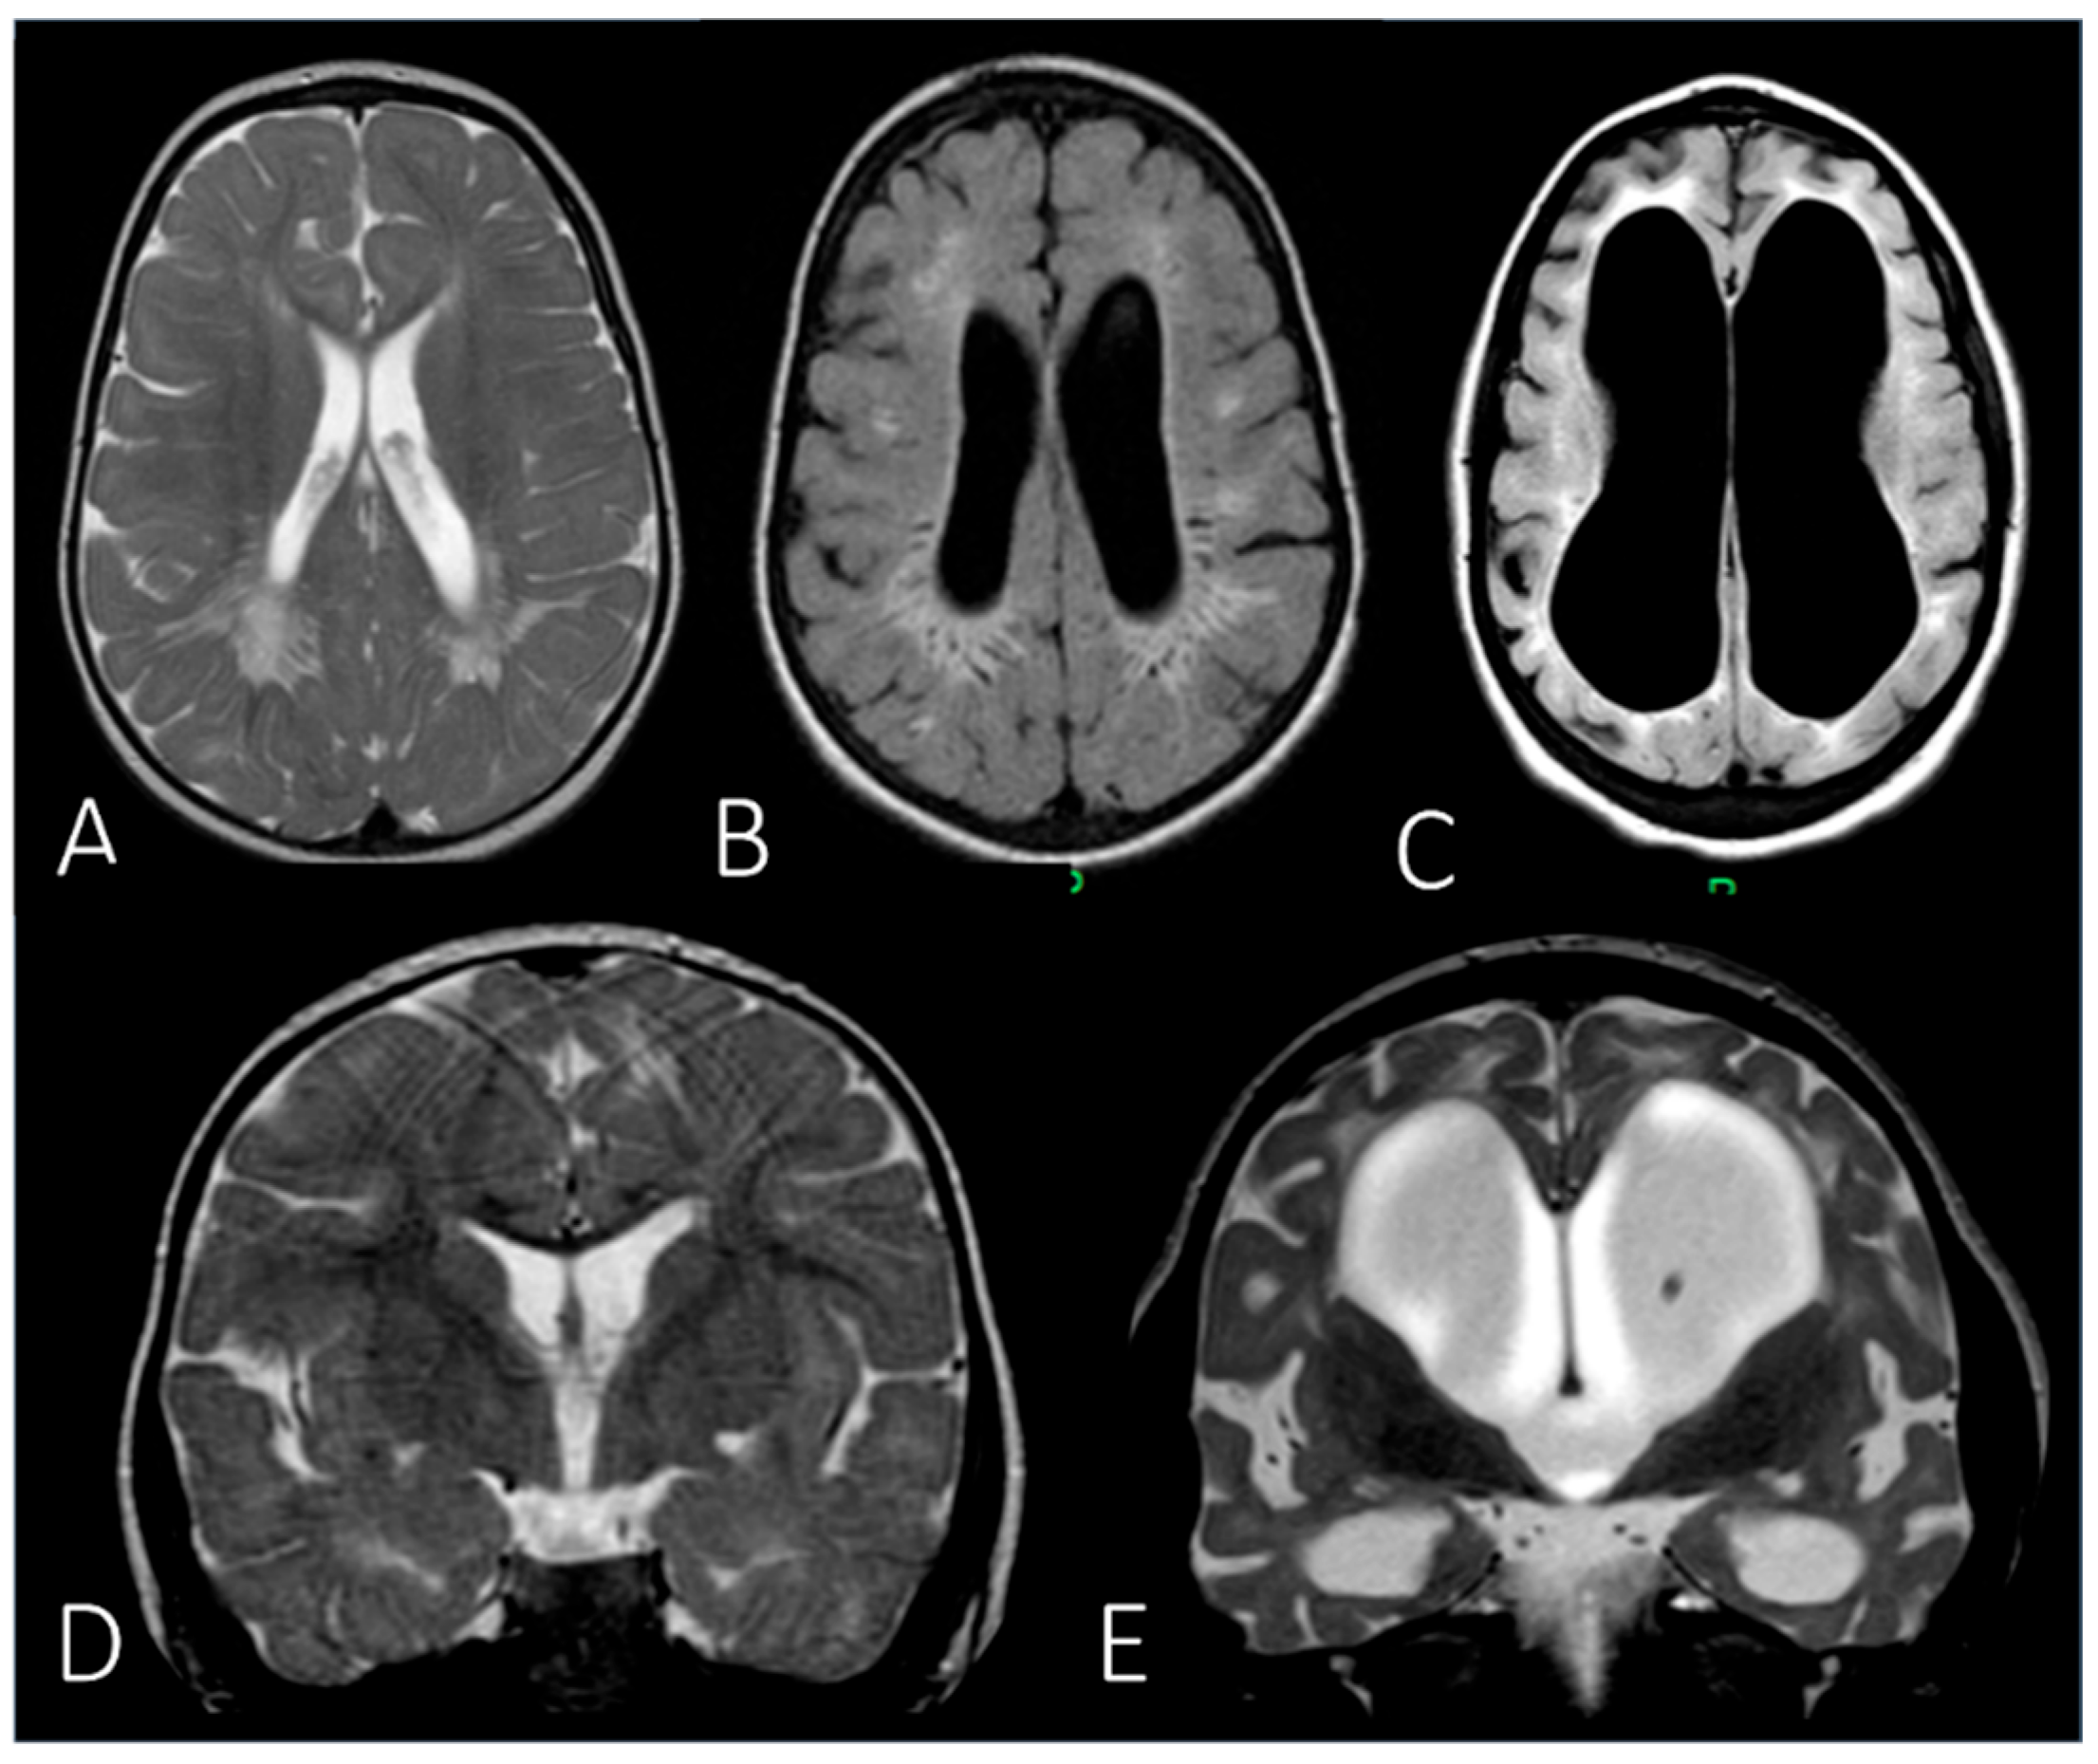

| MRI | Brain | Periventricular white matter abnormalities associated with enlarged perivascular spaces. | ||

| MRI | Brain | Extension of the white matter signal alterations; severe dilation of the ventricular system; cerebral atrophy. | ||